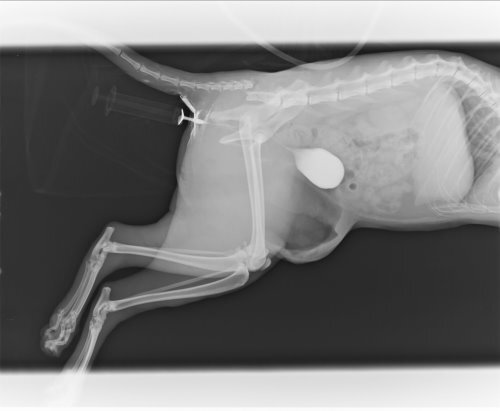

- 編號: 2005

主題: 車禍急傷 申請者姓名: 林素蘭 花色: 申請日期: 2013-06-03 23:43:51 申請者部落格: 申請者臉書網址: 所在縣市/合作醫院: 新北市/愛達司動物醫院 治療費用: 16867元 需求人數: 35人 已結案 (2013-06-27 14:20:08) 報名人員: philip x4(已付款)、Linda Wang(已付款)、Weili Chang x4(已付款)、吳毓軒 x2(已付款)、Emily Chou x10(已付款)、treaci(已付款)、賴霂菈(已付款)、黃亞凡(已付款)、戀糖bear x2(已付款)、你這樣(已付款)、Monica Wang(已付款)、點心(已付款)、小飛仔(已付款)、Kate(已付款)、miraai x2(已付款)、Bubu Wang x2(已付款)、 候補人員: sara1204、Suegie、 動物病情說明: 開車行經新店目睹貓咪被車子撞上,貓拖著雙腿在地上爬行,車來車往場面驚心,顧不得車上無任何工具,拿了厚塑膠袋衝到馬路上,試圖要抓牠,深怕這一錯過,貓就不見,或者一不小心又會被其他車輛撞到,一碰觸到貓,他立刻驚恐的想要掙脫,一回身拼命的咬,顧不得滿手鮮血,裝到袋子裡緊緊抱在懷裡,衝回去車上,打電話跟協會求助,送到協會配合的醫院,貓咪因為撞擊骨盆腔骨折,屁股附近的皮膚擦傷脫落,加上貓咪非常緊張,疼痛不願意進食,打了十幾天點滴,每天清創都唉唉叫,經過四十幾天的治療,屁股的傷口復原良好,因為骨盆尚未進行手術,怕癒後會有骨盆狹窄的問題,出院後先安置於家中照顧追蹤,大部分與到需要幫助的貓咪都會自己負擔醫療費用,但這隻貓咪傷勢嚴重,近期遇到的傷病需要醫療的貓咪很多,實在無力再負擔,自付三分之一的醫療費用八千多元,其餘還請各為幫幫忙。謝謝!